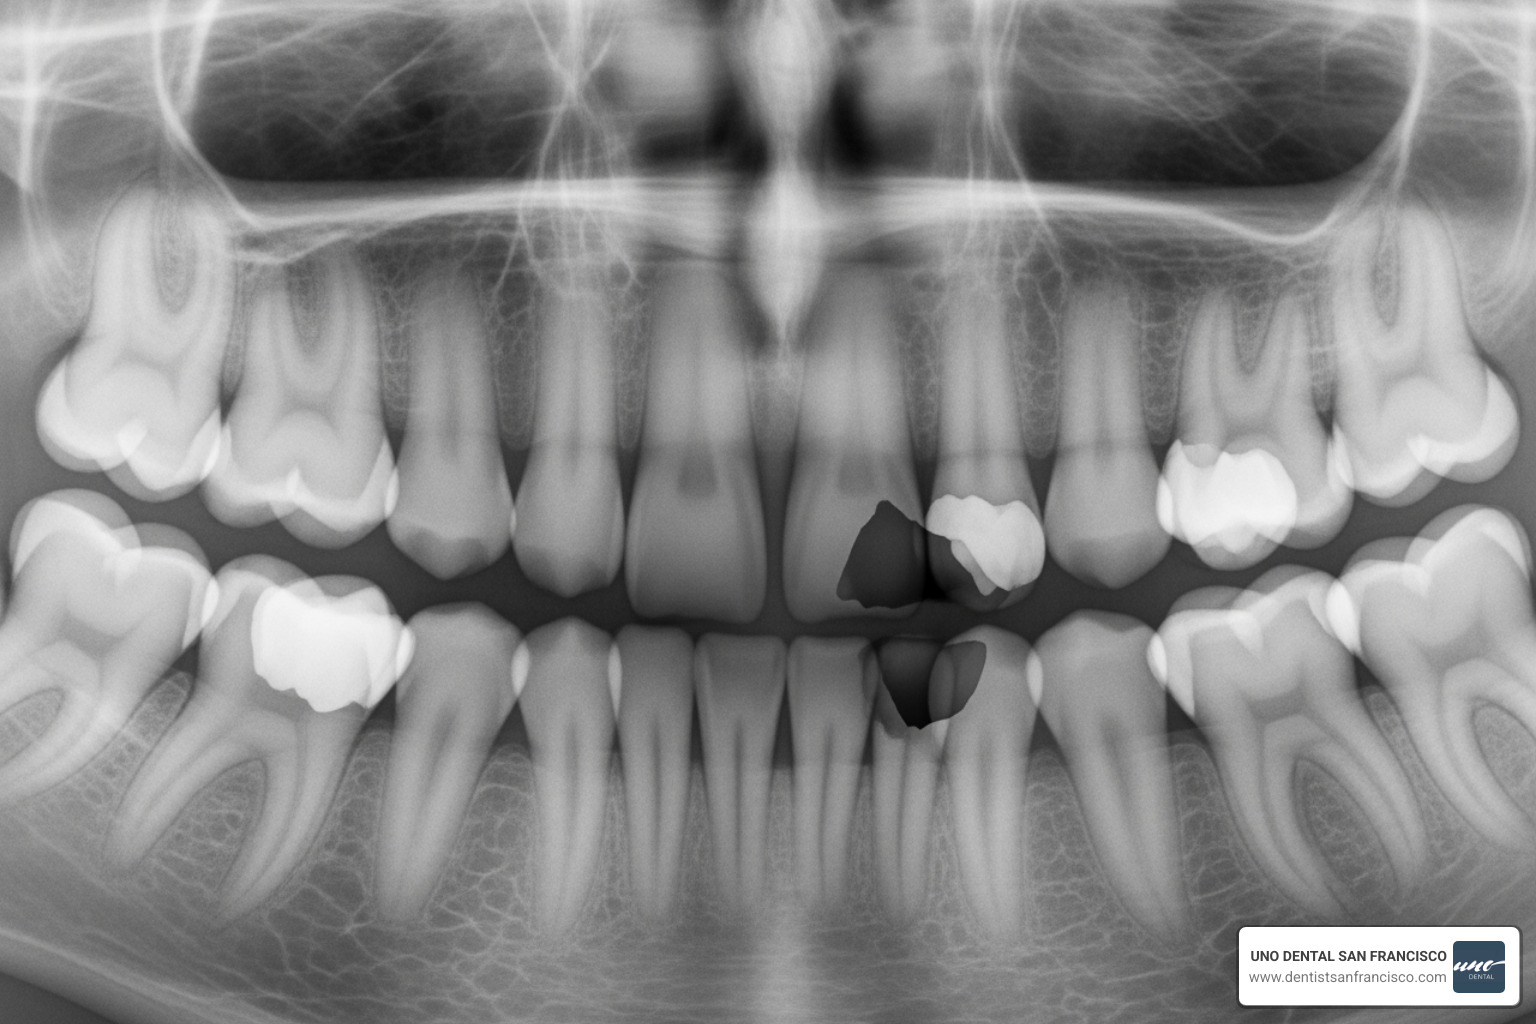

Panoramic X-rays offer a complete overview of all teeth, both jaws, and surrounding bones in a single image. The machine rotates around your child's head, so no sensor goes inside the mouth. This full mouth view is invaluable for spotting impacted teeth (including wisdom teeth), identifying extra or missing teeth, and evaluating overall jaw development.

Pediatric dental X-rays are especially important for orthodontic planning. They provide an invaluable window into your child's developing jaw and emerging permanent teeth.

During the critical years between ages 10 and 14, panoramic and cephalometric X-rays are crucial. These images allow us to:

- Monitor growth and development patterns and track permanent teeth.

- Identify impacted teeth (like canines or wisdom teeth) long before they cause problems.

- Analyze jaw and bite relationships to spot issues that may benefit from early intervention.

- Plan for braces by revealing the precise position of tooth roots, which is critical for moving teeth safely and effectively.